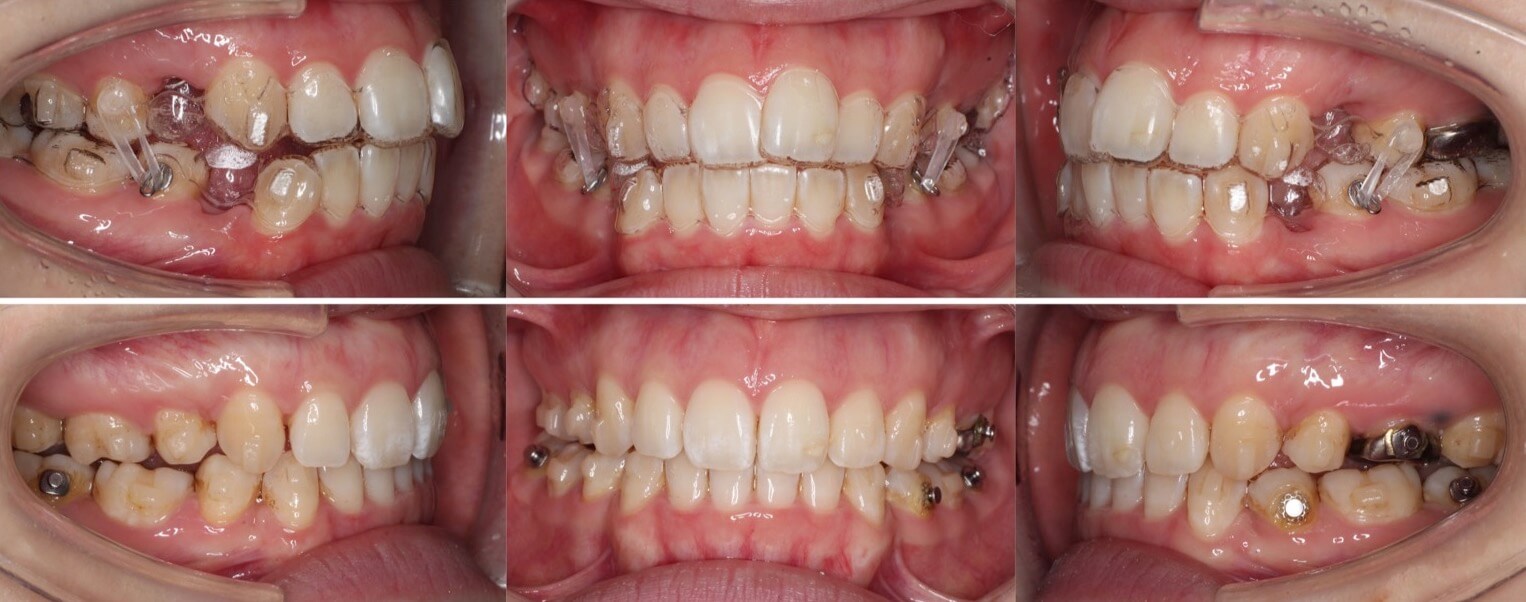

「目立たず口ゴボ改善」

20代女性・ハーフリンガル装置・前歯傾斜型

<症例概要> 難易度:★★★☆☆

主訴:口元の突出

年齢・性別:20代女性

住まい:千葉県船橋市

症状:上下顎前突・上下顎前歯唇側傾斜・開咬

治療方針:抜歯空隙の閉鎖(最大固定)

治療装置:ハーフリンガル矯正装置(上のみ裏側装置)

固定:歯科矯正用アンカースクリュー(口蓋側壁x2)

抜歯:上下第一小臼歯(計4本)

治療期間:2年8か月

リテーナー:上下クリアタタイプ+フィックスタイプ

治療費用:1,485,000(税込)

代表的副作用:痛み・治療後の後戻り・歯根吸収・歯髄壊死・歯肉退縮

▶︎その他の副作用

上下顎前突症に開咬症が併発している症例です。このように前歯のかみ合わせがかんでいない方、上の歯の裏側につける装置がつけやすくハーフリンガル矯正治療に向いています。治療後は上下の歯がしっかりとかみ合い、口元も後ろに引っ込みました。